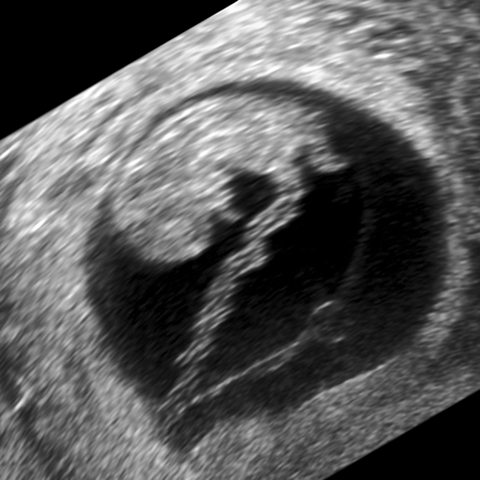

1st trimester pregnancy [2 of 3]